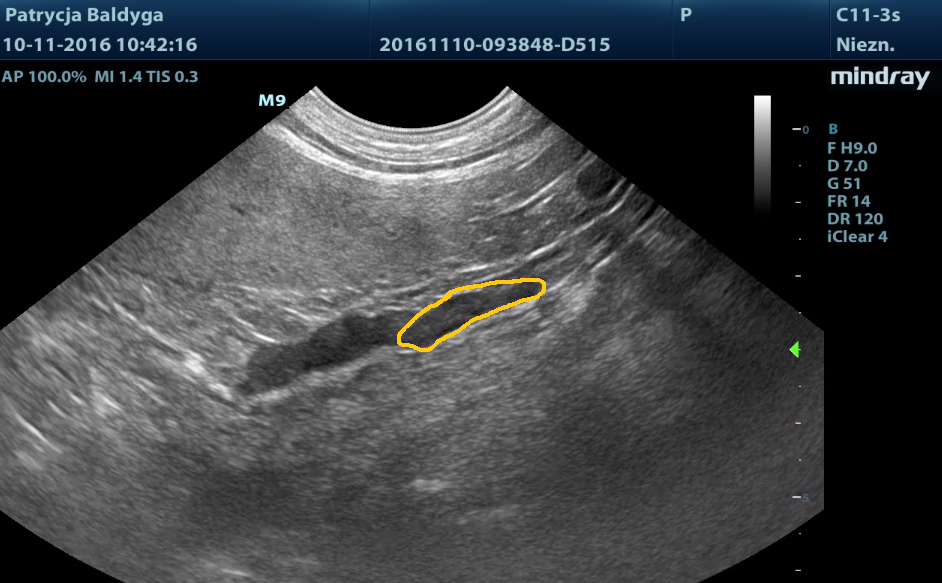

Okolicznie do lewej nerki obecność dużej, ok. 10-11 cm, owalnej struktury, heteroechogennej, w obrazie jak litej, jednak bez uchwytnego przepływu krwi (zdarza się, że nie wyłapujemy w badaniu dopplerowskim przepływu w drobnych, poskręcanych naczyniach, więc brak widocznego przepływu nie musi oznaczać braku unaczynienia zmiany).

Po dokładnym przeskanowaniu zmiany w różnych przekrojach wyraźnie widać, że jej pochodzenie jest nerkowe, obraz sugeruje duży guz nerki. Na niebiesko zaznaczona nieznacznie, do ok. 3 mm poszerzona miedniczka nerkowa, patrz: film i zdjęcie 2.

Ponieważ nie uwidoczniłam torbieli nerkowej, o której wspominała właścicielka, do głowy przyszło mi jej pęknięcie.

Pod uwagę brałam krwiak okalający nerkę, guz.